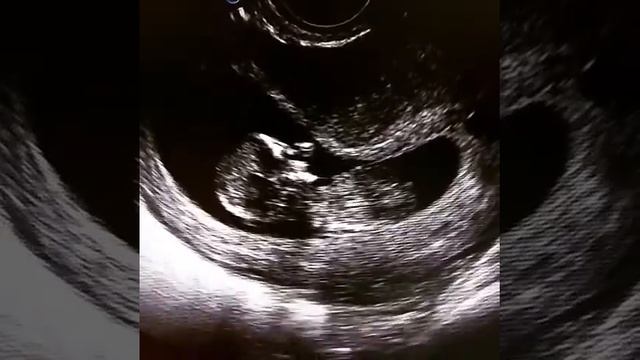

Узи ребенка в 5 лет

Узи ребенка в 5 лет 108 фотографий